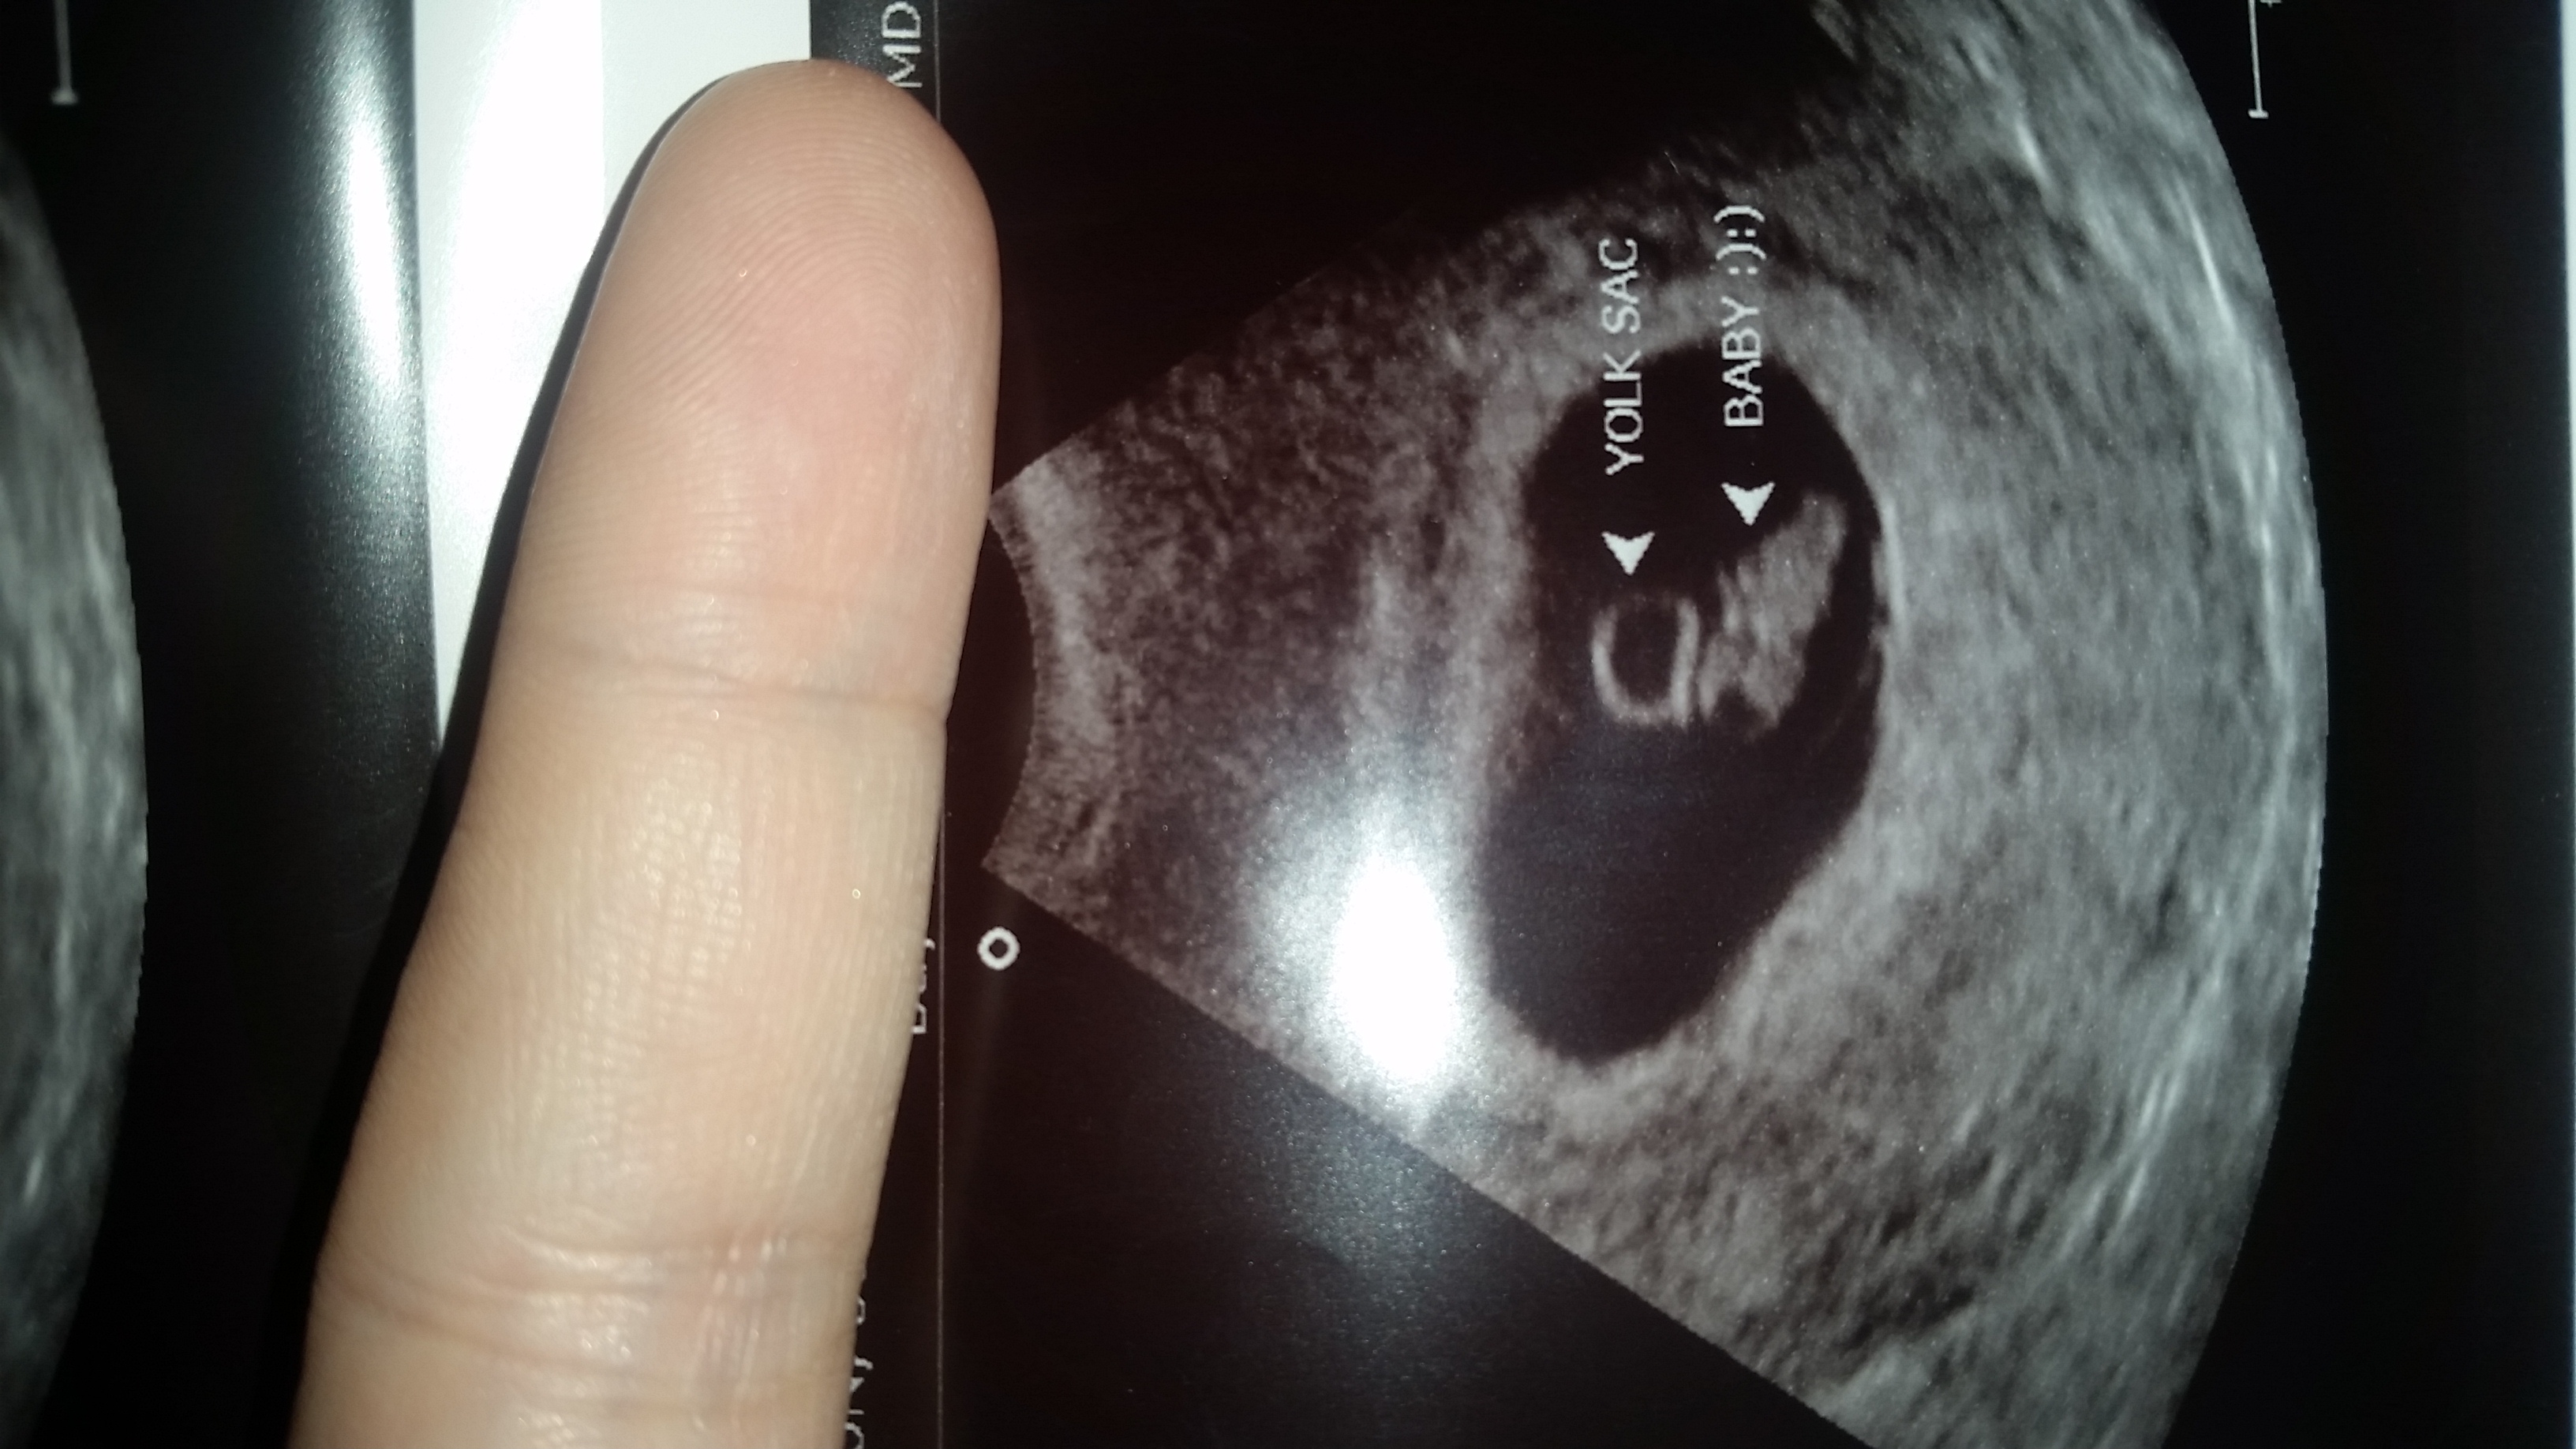

• So glad I get to finally post on this thread! First US today. I was really worries because my progesterone was low, but baby looks good :) heartbeat was 143. Not as far along as we originally thought, but not far behind. Right at 7 weeks. Due 2/23 :)